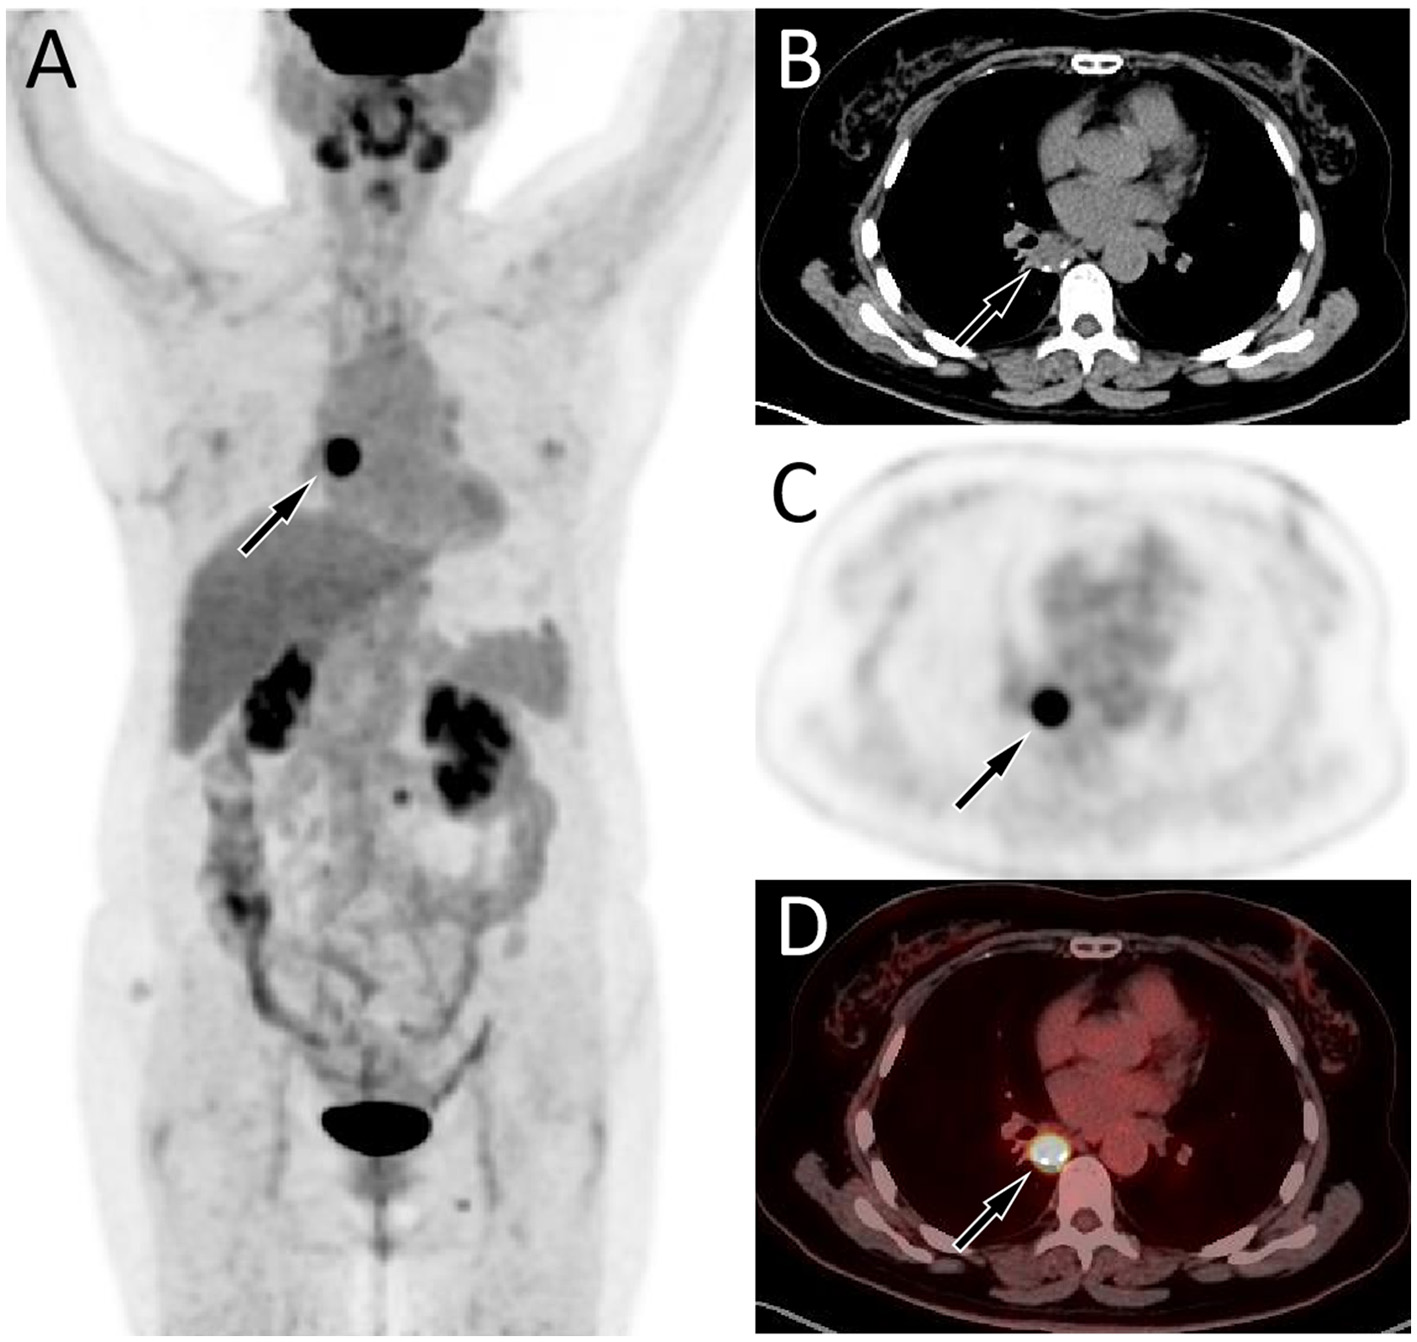

A 57-year-old female patient accidentally discovered a soft tissue mass in her posterior mediastinum during a physical examination in an outside hospital on 11 November 2023. She consciously had no obvious clinical symptoms and was not paid attention to, nor was undergoing any treatment. On 20 April 2024, the patient came to our hospital for medical help due to a cough and chest tightness. The physical examination did not reveal any positive signs. She and her family have denied any history of cancer or major genetic disorders. The serological laboratory test results revealed that the treponema pallidum antibody was positive, while other results, including blood routine, liver and kidney function, and serum tumor markers, were all negative. She had a history of syphilis 15 years ago; the condition resolved completely following treatment, and there are currently no clinical or serological indications of recurrence. She denied any history of tuberculosis, hepatitis, or malignancies. The patient underwent chest computed tomography (CT) examination (Figure 1) on April 24, which revealed a well-defined soft-tissue density mass in the posterior mediastinum with calcification. Contrast-enhanced CT showed a slight enhancement of the mass, suggesting a possible neurogenic tumor. The patient underwent surgical complete resection of the tumor through thoracoscopy under general anesthesia on April 26 after completing the preoperative routine examination. During the operation, the tumor was found to be located between the spine, azygos vein, trachea, and esophagus, with a size of approximately 6 cm × 4.5 cm × 4.0 cm, spindle-shaped, with a complete capsule and no obvious adhesion to surrounding structures. The tumor was gradually separated along its edges using an ultrasonic knife until it was completely removed, and then sent for pathological examination. Hematoxylin–eosin staining (as shown in Figure 2) showed that the excised tumor tissue appeared as a gray–red envelope block with intact capsule, medium texture, and calcified lesions in some areas. No tumor invasion was observed at the resection margin. Immunohistochemistry revealed tumor cells positively expressed vimentin, Cluster of Differentiation 34 (CD34), cytokeratin (CK), and CD56, while they negatively expressed insulinoma-associated protein 1 (INSM1), S100, CD68, and so on. Based on these histopathological findings of the patient, she was diagnosed with PES. After surgery, the patient did not receive further radiotherapy, chemotherapy, or other treatment methods. At 4 months after discharge, a chest CT examination revealed a new soft tissue density nodule at the site of her previous surgery. In order to further evaluate the nature of the nodule and determine the next treatment plan, the patient underwent 18F-FDG PET/CT imaging (as shown in Figure 3) on August 20. The results showed that the above nodule, as shown on CT, showed a significantly increased 18F-fluorodeoxyglucose (18F-FDG) uptake, while no significant hot spots were observed in the rest of the body. These imaging findings suggested the possibility of local recurrence of the tumor, and due to the limitation of the lesion, the surgeon planned to perform a second operation on her. However, the patient refused surgery again. On October 16, the patient returned to the hospital for chest pain and underwent chest CT examination (Figure 4), which showed that the mass was significantly larger than before. Currently, she is receiving a chemotherapy regimen of epirubicin in combination with isocyclophosphamide.

Figure 1

Chest computed tomography (CT) mediastinal window (A) revealed a soft tissue density mass (black arrow) about 4.6 cm × 3.2 cm in size with nodular calcification (red arrow) can be observed on the right posterior mediastinum; (B) The coronal view shows that the tumor is spindle shaped (arrow); In the arterial phase (C) and vein phase (D) of contrast-enhanced CT, the lesion showed mild uneven enhancement (arrows); In the delayed phase (E, axial, F, sagittal), the enhancement of the mass gradually diminishes (arrows).